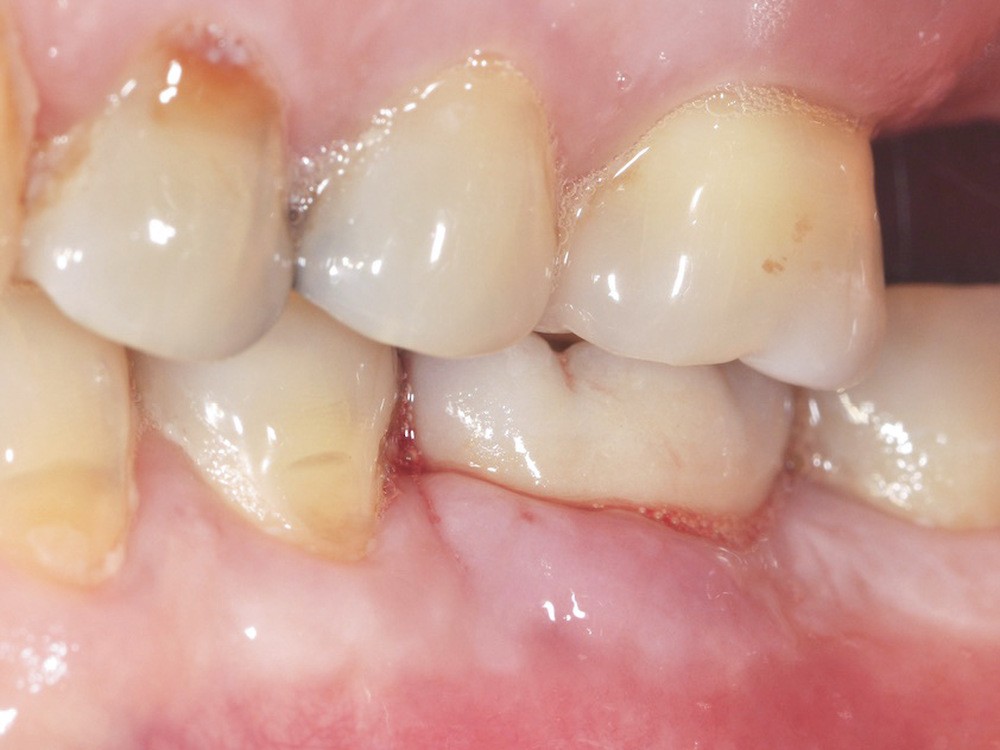

– la mucosite péri-implantaire, définie comme une inflammation réversible des tissus mous péri-implantaires sans atteinte osseuse (fig. 1a, b) ;